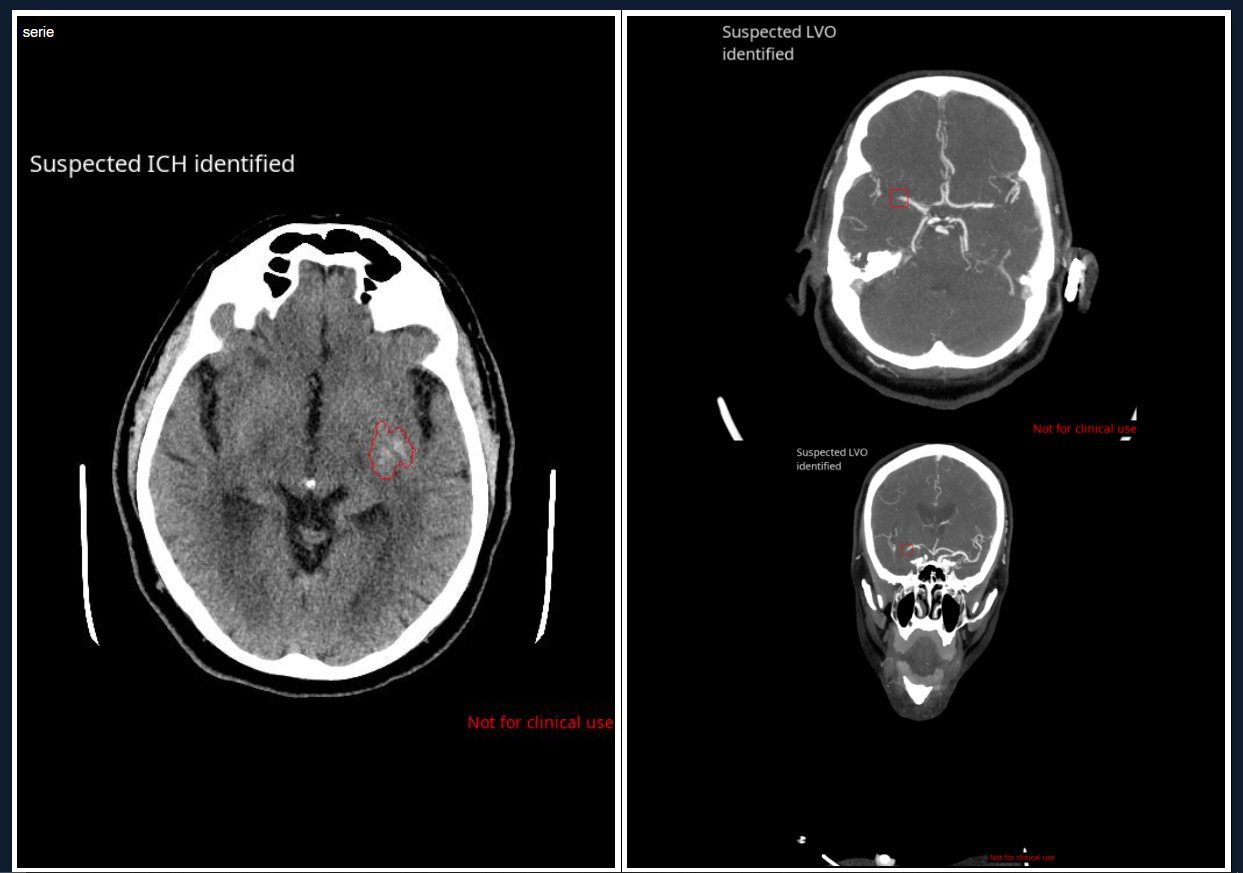

En los últimos años, la inteligencia artificial (IA) ha dejado de ser una promesa futura para convertirse en una herramienta fundamental en los[…]